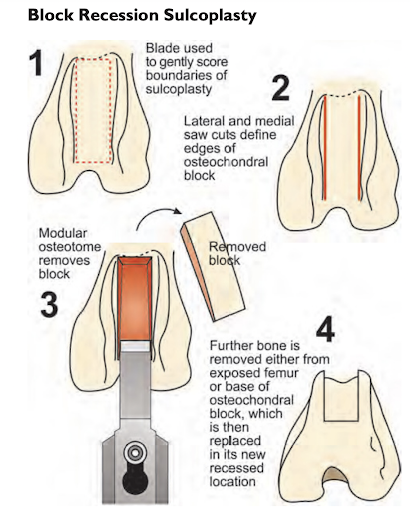

- Sulcoplasty

- Deepening of the groove where the patella normally sits in to create stability using either a block recession sulcoplasty or wedge recession sulcoplasty (Figure 4 and 5).

Figure 4: Block recession sulcoplasty (Veterinary instrumentation 2019, https://www.petvetbiomed.com/html5/web/10200/36779ImageFile3.pdf)